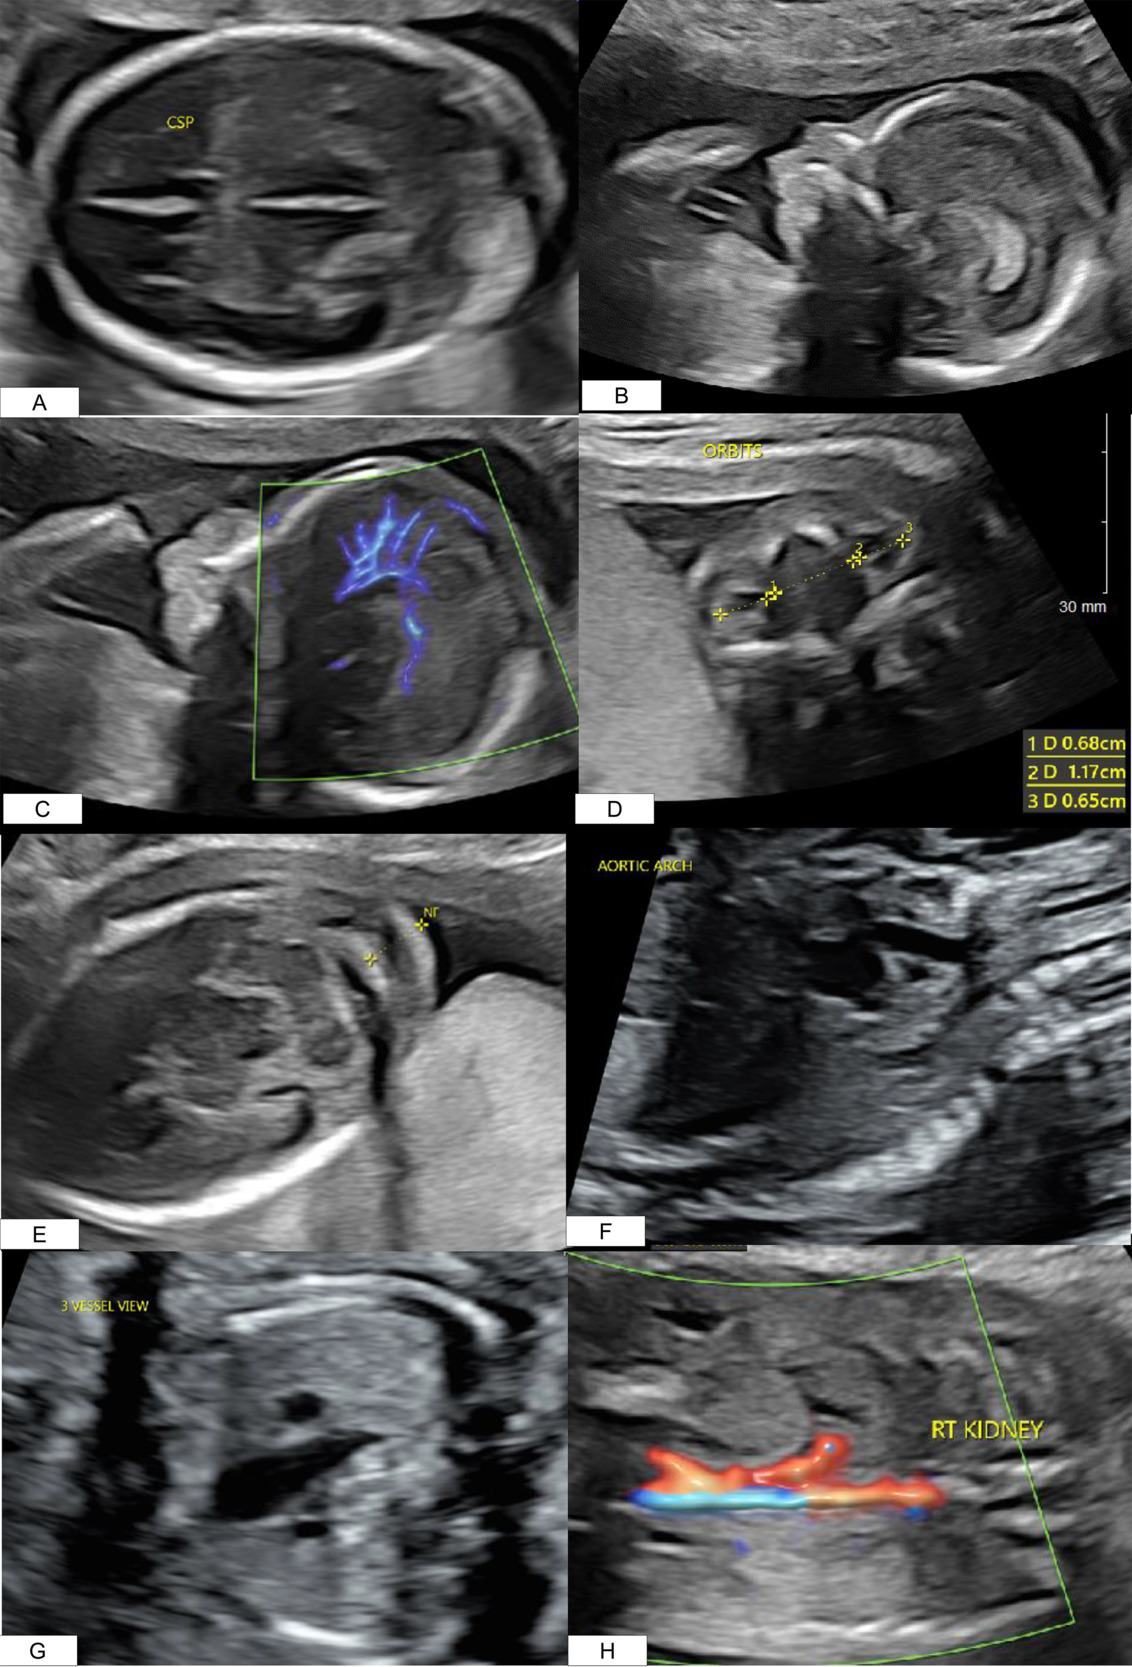

A 41-year-old Gravida 3 Para 2002 presented for a routine anatomical survey at 20 weeks. Several anomalies were noted: an absent cavum septum pellucidum (Figure 1A), micrognathia (Figure 1B), abnormal pericallosal artery (Figure 1C), hypertelorism (Figure 1D), nuchal fold thickening (Figure 1E), a complex cardiac defect (Figure 1F and 1G), and an absent left kidney (Figure 1H), Additional findings are listed in Table 1A. Amniocentesis revealed an abnormal male karyotype: Trisomy 22 (47, XY +22) (T22) (Table 1B). Microarray detected mosaic gain, around 80%, of all markers on chromosome 22 (Table 1B). Amniotic fluid alpha-fetoprotein was analyzed and found to be within normal range. Fetal echocardiogram identified a double outflow from the left ventricle, a large ventricular septal defect, and a possible mispositioning of the great arteries without alterations to flow throughout the ventricles or the great vessels.